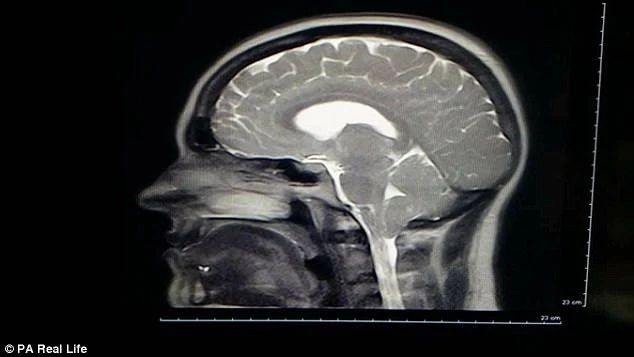

Khi đi khám, cô được bác sĩ kê thuốc giảm đau và thuốc viêm khớp, nhưng cơn đau không những không giảm mà còn tăng lên. Sau một tháng, cô tiếp tục vào bệnh viện và được quét MRI, lúc này các sĩ phát hiện bất thường trên não cô và kết luận cô bị bệnh hiếm Spontaneous Intracranial Hypotension.

Nguyên nhân thường gặp nhất dẫn tới căn bệnh này là áp suất trong khoang não hạ thấp, màng dịch sẽ bị thủng hoặc rách một lỗ gây rò rỉ. Sau khi phẫu thuật đóng các lỗ rò trên màng dịch não vào tháng 12-2015, cơn đau của cô giảm xuống đôi chút. Nhưng sau 1 tai nạn xe hơi vào tháng 6-2016, các triệu chứng trước kia trở lại.